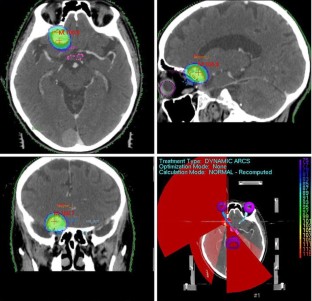

A total of 22 patients with ACM were treated using HFSRT. Frameless image guided volumetric modulated arc therapy (VMAT) was performed with a 6 MV linear accelerator (LINAC). The total dose was 25 Gy delivered in five fractions over five consecutive treatment days. Local control (LC) and progression free survival (PFS) rates were calculated using the Kaplan–Meier method. Common Terminology Criteria for Adverse Events, version 4.0 was used in toxicity grading.

Fig. 1

Fig. 2